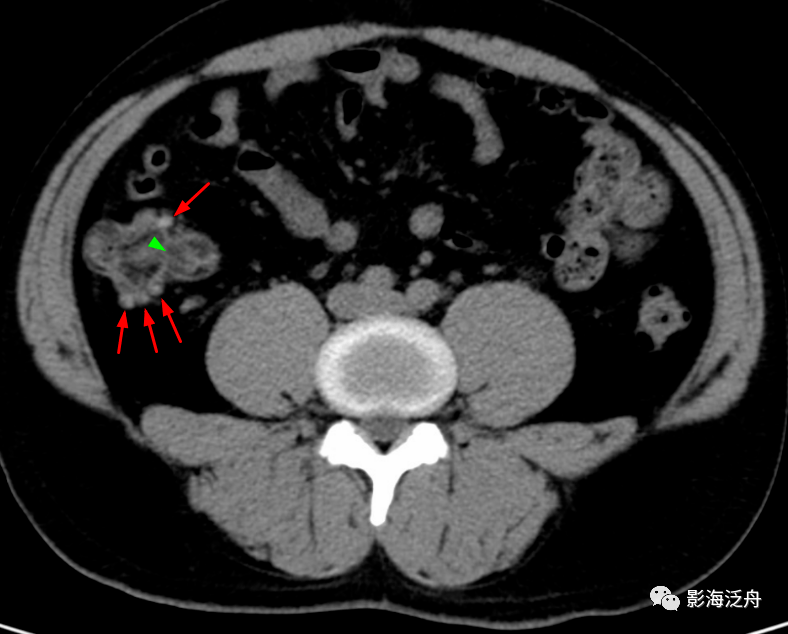

粗(管腔直径>7mm)阑尾壁增厚(大于3mm)阑尾粪石阑尾周围脂肪内条纹影

(3)ct检查:平扫见右下腹阑尾内粪石,阑尾增粗,管壁毛糙,周围脂肪间隙